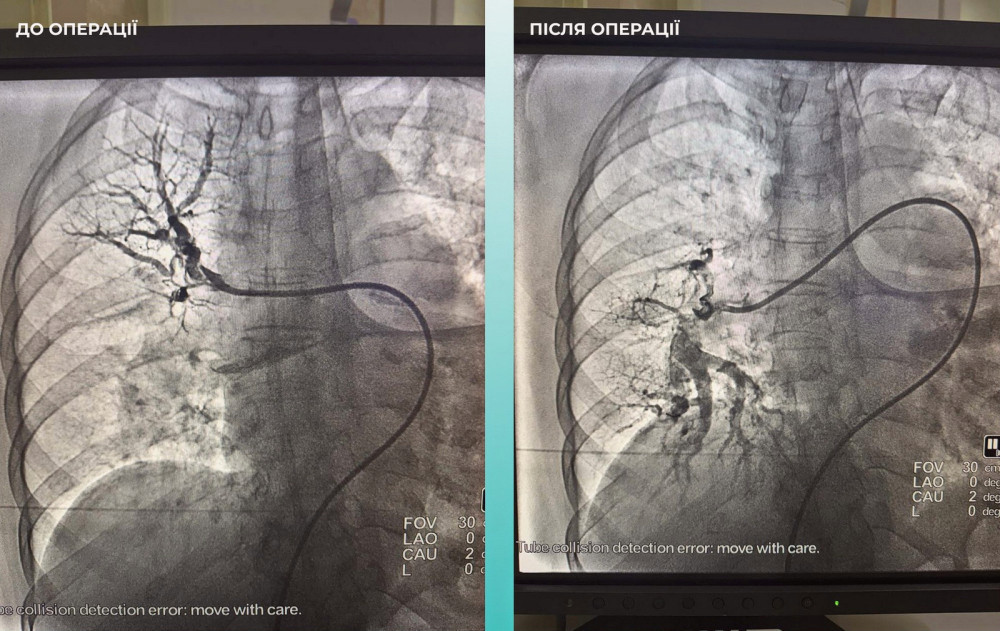

Команда лікарів ухвалила важливе, але складне рішення — провести одночасну тромбектомію для обох артерій.

Операція пройшла вдало. Наразі пацієнтка почувається значно краще: вона при свідомості і може рухати кінцівками.